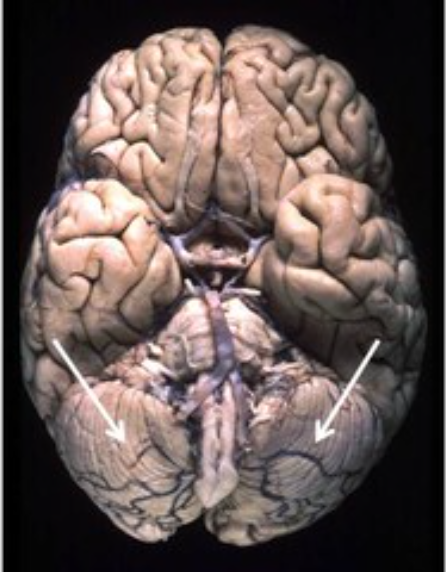

The indicated area is supplied by what artery?

posterior inferior cerebellar